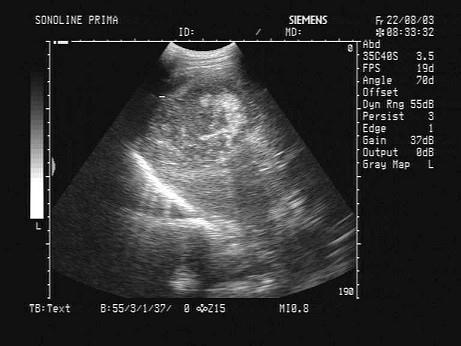

某患者25岁,高热,肝区疼痛。肝脏声像图表现如图,结合病史,最可能的诊断是?(?)A.肝血管瘤B.肝脓肿C.肝硬化D.肝癌E.肝囊肿

问题 某患者25岁,高热,肝区疼痛。肝脏声像图表现如图,结合病史,最可能的诊断是?(?)

选项 A.肝血管瘤 B.肝脓肿 C.肝硬化 D.肝癌 E.肝囊肿

答案 B